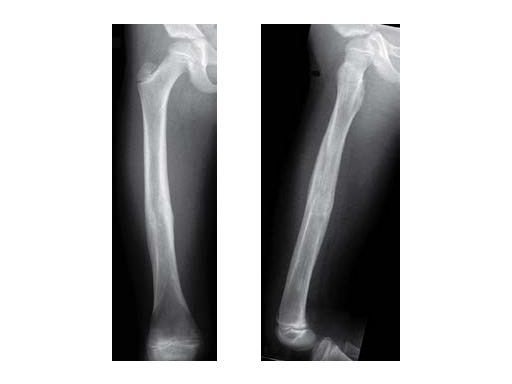

Introduction During the last two decades, elastic stable intramedullary nailing (ESIN) has become the method of choice for internal fixation of femoral and tibial shaft fractures in children of 414 years of age. In the lower extremity, ESIN treatment may be complicated by loss of reduction following push-out of the nails at the entry site especially in unstable femoral shaft fractures. The rate of this complication, nail migration with subsequent soft-tissue and skin irritation was reported to be as high as 512 %. A technically simple method to achieve secure locking of ESIN was not available so far. An end-cap system for ESIN that is now available which locks the nails at the entry point was evaluated clinically. The end caps are equipped with a self-cutting device and are put over of the cut ends of the nails like a hollow screw that is fixed in the cortical bone at the nail entry site.

Methods 34 femoral shaft fractures in pediatric patients were treated by ESIN and end caps at the Department of Pediatric Surgery in Berne from January 2005 to January 2009. Fractures of an unstable type and higher weight or older age of the children were considered as an indication to add end caps to ESIN. Results were evaluated as to applicability of the end-cap system, fracture type, instrumentation stability, and fracture healing, and return to activity by analyzing patient charts, x-rays, and questionnaires including follow-up data.